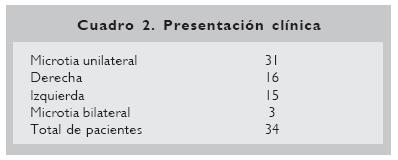

Se incluyeron 34 pacientes con microtia, 20 del sexo masculino y 14 del sexo femenino (Cuadro 1), con una edad promedio de 9.5 años (n =7–12 años). Se incluyeron 31 pacientes con microtia unilateral y tres con microtia bilateral. Dentro de la presentación clínica unilateral, no se encontró diferencia en la presentación derecha (n =16) o izquierda (n =15) (Cuadro 2).